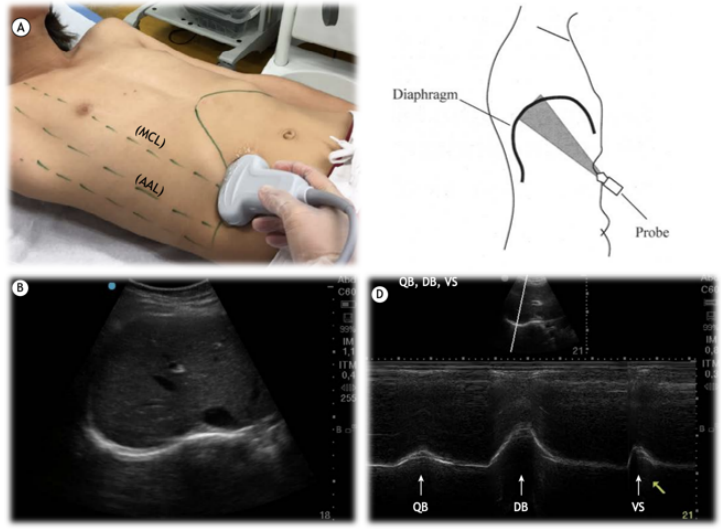

临床中进行膈肌管理要秉持的基本思路和方法主要包括四部分:①风险识别和防治:例如脓毒性休克,血管活性药物或激素的使用,营养不良,高强度有创机械通气等。患者越快度过危重期,膈肌功能保留就越好,后期撤机就越简单。②膈肌的训练:要采用各种手段,使患者的膈肌动起来,包括尽早恢复自主呼吸和膈肌活动,呼吸支持力度降阶梯,PSV模式,膈神经起搏,膈肌阻抗训练等。③膈肌功能评估:包括评估最大吸气压(MIP),通过超声评估膈肌厚度、变异度及膈肌活动度。④膈肌做功状态评估:识别患者的异常呼吸状态及呼吸疲劳,评估辅助呼吸肌的参与、呼吸驱动及人机同步性。2022年四川大学华西医院周永方等在Crit Care发表了一项随机对照研究,证明了浅镇静可以缩短患者机械通气时间,提高拔管成功率。笔者团队的经验是,浅镇静和早期膈肌锻炼是防治膈肌功能障碍最有效的手段。我们的目标是通过浅镇静和自主通气模式来使患者维持接近自然呼吸的驱动,丙泊酚和右美托咪定可能最契合。同时,在使用PSV模式时,设置PS使患者的呼吸驱动在正常范围。如果短时间内患者的自主呼吸不能完全恢复,或由于某些情况不能短时间内唤醒,或因为神经功能障碍等问题短时间内不能拔管,患者长期带机很可能导致膈肌萎缩,此时就需要通过膈神经起搏来预防膈肌衰弱。膈神经起搏目前尚处于研究阶段,但有些医院已将其作为常规的治疗手段,该方法更多是预防膈肌萎缩。其机制是通过体外膈肌起搏器刺激膈神经使膈肌运动,进而达到预防膈肌萎缩的目的。已有动物实验证实有创机械通气期间的膈神经起搏可以降低膈肌纤维的变薄趋势。也有研究发现机械通气期间的膈神经起搏可以降低膈肌变薄趋势。最早的膈肌起搏是体内植入电极,主要用于有外周神经系统功能障碍患者,可以通过中心静脉给予刺激,也可以在患者锁骨中线第二肋间处植入起搏器。对于重症患者,通常采取体外膈肌起搏(EDP),在体表靠近膈神经处贴1~2组电极片,连接刺激器。每天2次,每次30 min,每周5天,频率为8~20次/min,能够预防膈肌萎缩。该方法通常需要进行质控。通过监测患者的呼吸机波形、膈肌超声以及患者主诉/面容等了解治疗情况。3. 膈肌训练—drive the diaphragm膈肌训练一般是通过膈肌阻抗训练来完成。也有学者认为重症患者早期下床活动可以达到锻炼膈肌的效果,但目前没有得到研究证实。我们通常所说的膈肌训练指的就是膈肌的阻抗训练,并且是目前唯一被高质量研究证实的可以改善患者膈肌功能的治疗措施。2023年Eur Respir Rev杂志发表的研究表明,膈肌阻抗训练能够增加患者的MIP、提高生活质量。目前机械式膈肌阻抗训练器有两种类型,一种是流阻负荷训练器,另一种是阈值负荷训练器。流阻负荷训练器是通过调节旋钮孔径的大小来调节吸气阻力,孔径越小阻力就越大。缺点是比较依赖于患者的吸气流速。所以在整个训练过程中其阻力是不稳定的,效果可能也不如预期。而阈值负荷训练器的的阻力在整个训练过程中比较稳定,能够比较好地保证训练效果。目前的研究大都推荐首选阈值负荷训练器。无论是健康人还是慢阻肺人群,阈值负荷训练器的压力都更稳定,训练效果更佳。机械式阻抗训练器可以直接连接人工气道。在机械式阻抗训练器缺乏的情况下,也可以将呼吸机的触发方式改为压力触发,增加压力触发灵敏度的数值,也就是增加触发难度,同样可以达到训练的目的。此外,如果患者膈肌功能特别差,也可以接螺纹管,训练几天后再过渡到上述两种方法。膈肌训练的原则是高强度、低频率。如果患者能够配合,可以直接采用手持式测力器或简易肺功能仪来测量。如果患者配合度不好,或患者镇静尚未清醒,可以通过呼吸机的NIF或MIP功能,长按20~25 s来读数,可以测量患者的MIP,测出后从50% MIP设置,连续6次呼吸,每天5组,每周不少于5天,组间休息1~2 min。按照MIP的50%设置阻力强度。膈肌训练适应证:机械通气预计或已经达到1周以上。训练方法:训练器、增加呼吸机触发难度;MIP过低的患者,可以使用螺纹管。需要每天滴定阻力值,至患者刚好完成连续6次呼吸,而不引起明显膈肌疲劳。正常来讲,如果训练效果好,患者MIP平均每天会增加1 cmH2O。澳大利亚重症指南推荐患者至少坚持训练2周。最好能坚持1个月。训练期间注意加强心理辅导和营养支持。体外膈肌电刺激和膈肌训练是目前在ICU中针对膈肌的治疗和训练。除了训练,还要注意做好膈肌功能的评估,判断治疗后患者膈肌功能有无好转。常用的评估方法有膈肌超声。(1)膈肌超声:膈肌超声有两个测量位置,一个是在锁骨中线与肋弓下缘交界处,测量膈肌的移动度。如图1B和D所示高亮白线就是膈肌的位置,在患者正常呼吸时,采用M模式测量浅呼吸和深呼吸下膈肌的移动度。另外一个测量位置是在腋中线或锁骨中线8~10肋间,通过M模式测量膈肌在吸气末和呼气末的厚度(如图2所示),从而判断膈肌做功情况以及膈肌增厚率,这些参数能够反映膈肌功能。此外,膈肌超声还可以帮助判断膈肌是否萎缩、衰弱,并预测撤机风险。表1所示为安静呼吸、深呼吸和鼻息试验时膈肌的正常移动度。如果测得的患者膈肌移动度低于表中数值,说明患者膈肌已经萎缩。Intensive Care Medicine杂志发表的一篇综述中给出了诊断建议:如果患者最大膈肌增厚分数<20%,可以认为该患者存在膈肌萎缩或膈肌无力;或嘱患者做深呼吸,观察患者最大膈肌移动度是否超过1 cm,也可以帮助判断患者有无膈肌萎缩。